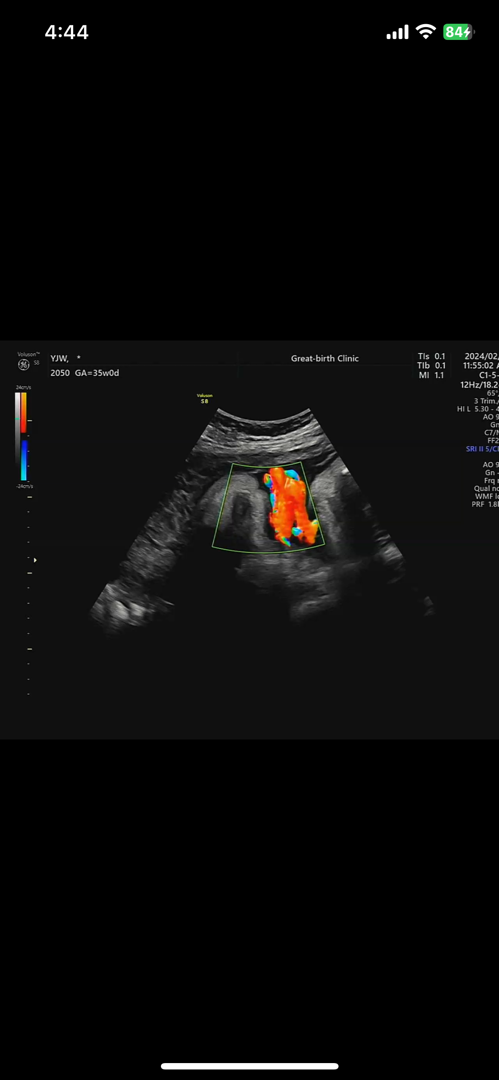

아기가 탯줄을 목에 두번감고있다는데요

자분해서 낳을때 별 문제 안될까용?? ㅠ 걱정이되네용🥹 애가 커서 38주에는 유도해야할거 같거든요

저는 지난주에 한번 감고 있었는데 이번에는 풀렸더라수요. 의사말로는 탯줄이 짧은거 아니면 나올때 목을 조이지 않고. 아기 바이탈 체크를 하기 때문에 문제 되는 경우가 드물데요.